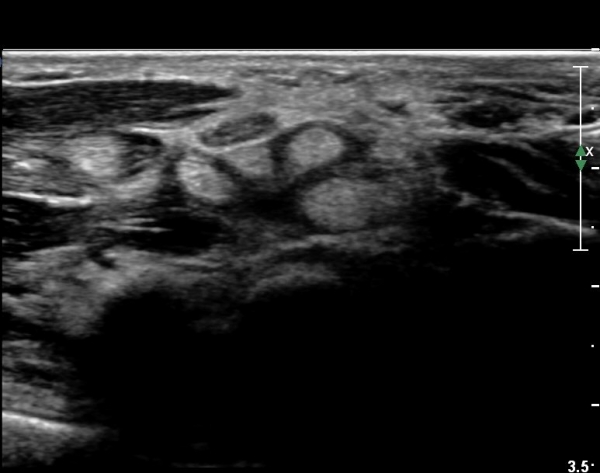

¼Õ¸ñ°ú ¼ö±Ù°ü±ÙÀ§ºÎ Ⱦ´Ü¸é°Ë»ç¿¡¼­  ÈûÁÙÀÇ ºñÈÄ¿Í ÈûÁÙ ÁÖÀ§ Ȱ¾×¸· ºñÈİ¡ °üÂûµÇ³ª

Á¤Áß½Å°æ ºÎÁ¾Àº °üÂûµÇÁö ¾Ê´Â´Ù(»çÁø 3, 4).